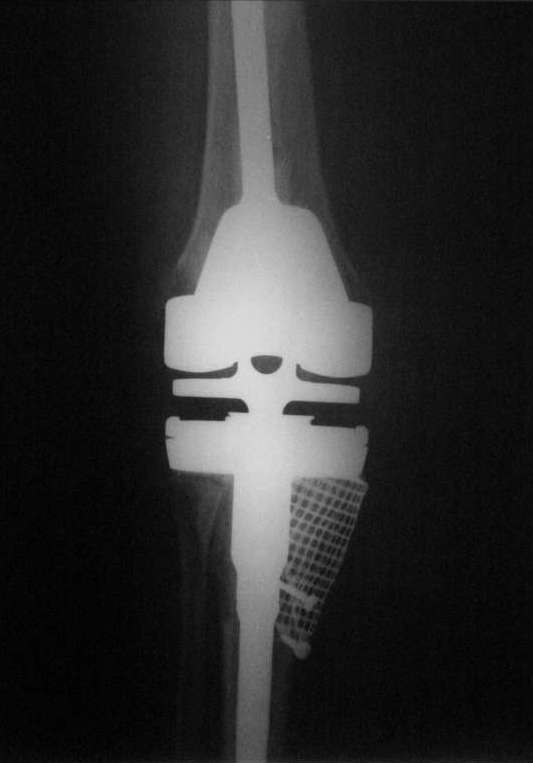

Как я уже писал ранее, пациентке до этого дважды устанавливались первичные протезы, выполнялась лавсанопластика внутренней коллатеральной связки.

Уже при первичном эндопротезировании большеберцовая кость была резецирована на 0.5 см. ниже головки малоберцовой кости с существенным варусом.

При ревизии с установкой второго протеза (обычного PS) ситуация ухудшилась еще в еще большей степени + ножка тибиального компонента пробила наружный кортикал большеберцовой кости.

Вдобавок ко всему все это ещё и нагноилось.

Пациентка обратилась к моему хорошему знакомому.

Мы посоветовались и решили удалить все и поставить спейсер на 3- 4 месяца, провести курс антибиотиков.

После установки спейсера рана зажила хорошо.

От артродеза пациентка отказалась и мы рассматривали 2 варианта:

1) Установить онкологический протез GMRS Stryker с резекцией проксимального конца большеберцовой кости.

2) Установить простой hinge MRH Stryker с костной пластикой дефекта.

Мы предпочли второй вариант. (Отдельное спасибо А.В. Каминскому за интересную статью).

Примерно через 4 месяца после установки спейсера мы пошли на ревизию.

После открытия сустава оказалось, что головка малоберцовой кости возвышается над наружным кортикалом большеберцовой кости на 1 см, а над разрушенным внутренним мыщелком на 3 см (см. фото).

Рассверлили канал большеберцовой кости. В канал поставили стержень. По нему, на наружный кортикал посадили шаблон тибиального компонента (см. фото). Определили размер дефекта внутреннего мыщелка, который надо закрыть сеткой.

На внутренний мышелок установили сетку из нержавеющей стали Ex-Change Stryker (предназначенную для укрепления верхнего края вертлужной впадины) и фиксировали её 4 винтами. Подрезали сетку сверху по шаблону тибиального компонента. После этого рассверлили канал б/б и бедренной костей под протез. Используя систему пульс-лаважа Stryker SurgiLav c насадкой - щеткой для промывания каналов промыли бедренную и большеберцовую кости. Последнее сверло, которым рассверливали проксимальную часть канала б/б кости, оставили на месте. Аллотрансплантат перемололи на костной мельнице, перемешали с 3 гр. ванкомицина и достаточно плотно заполнили им дефект внутреннего мыщелка, утрамбовывая импактором костную стружку в единую массу.

Так как наружный кортикал был на 1.3 см. ниже головки малоберцовой кости, пришлось использовать вставку под большеберцовый компонент 1 см. На цемент c ванкомицином поставили тибиальный компонент с ножкой 11/80 мм.

Бедро по шаблону резецировали (лучше сказать «причесали»). Системой пульс-лаваж с щеткой для отмывания костной поверхности основательно все отмыли и поставили на цемент бедренный компонент c ножкой 11/155 мм.